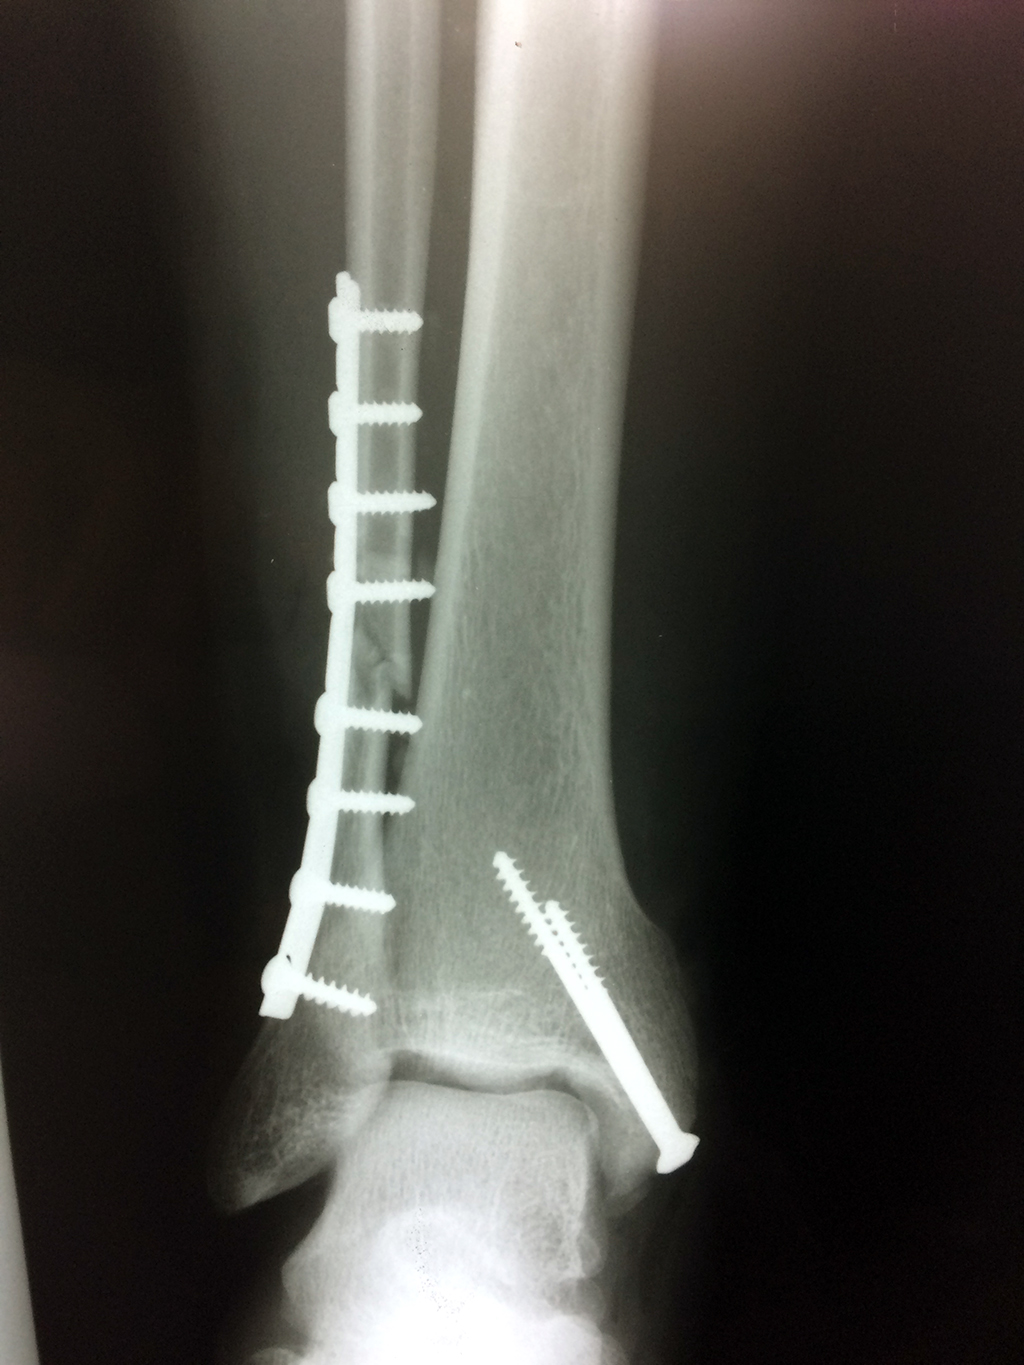

Cuando se necesita cirugía, es probable que esta implique el uso de clavijas de metal, tornillos o placas para sostener los huesos en su lugar mientras la fractura se consolida. Los elementos de soporte pueden ser temporales o permanentes.

Cirugía de Tobi...

Detail Download